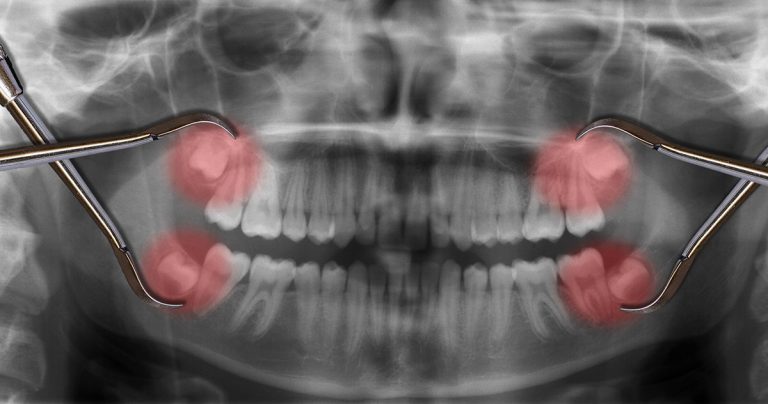

Les dents de sagesse, également appelées troisièmes molaires, apparaissent généralement entre 15 et 25 ans. Elles sont le plus souvent au nombre de quatre, mais il est possible qu’il n’en existe que trois, deux, voire aucune. Selon leur position, elles peuvent être sur arcade, enclavées ou incluses sous la gencive.

Chaque intervention débute par une consultation permettant d’évaluer la position des dents de sagesse et de déterminer la nécessité de l’extraction.